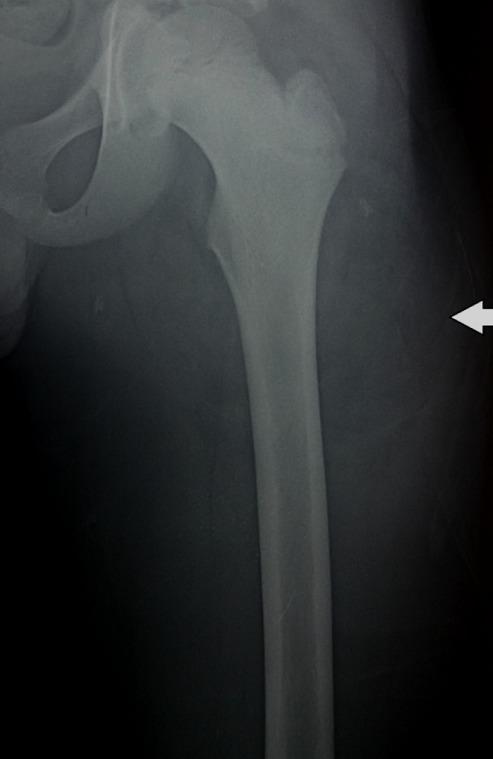

Lipoblastoma is a relatively rare benign tumor. It derives from embryonic white fat cells. It almost exclusively affects children less than 3 years of age. We report a case of lipoblastoma of the left thigh detected in an older child (11 years) and a literature review. Diagnosis was based on histology while surgical treatment was based on total resection of the mass. The postoperative course was simple with a follow-up period of 9 months.

脂肪母细胞瘤是一种相对罕见的良性肿瘤。它起源于胚胎白色脂肪细胞。几乎仅发生于3岁以下儿童。我们报告1例在大龄儿童(11岁)中发现的左大腿脂肪母细胞瘤病例并进行文献复习。诊断基于组织学检查,而手术治疗基于肿物的完整切除。术后过程顺利,随访期9个月。